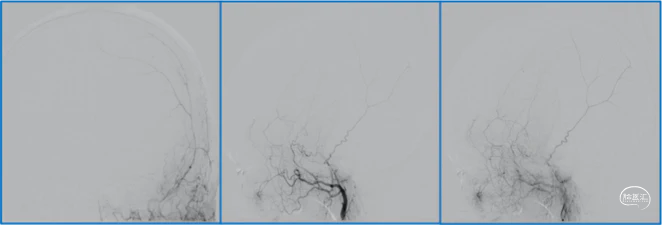

典型病例

![]()